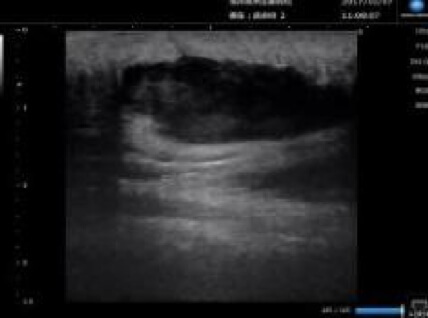

超音波診断装置

超音波を用いた皮下腫瘍の診断や、外傷時の皮下異物などの診断に役立ちます。視診、触診だけではわからない情報をたくさん得ることができます。患者さんは痛みもありませんので、子供さんでも検査を受けることができます。

コニカミノルタの超音波機器を導入しています。